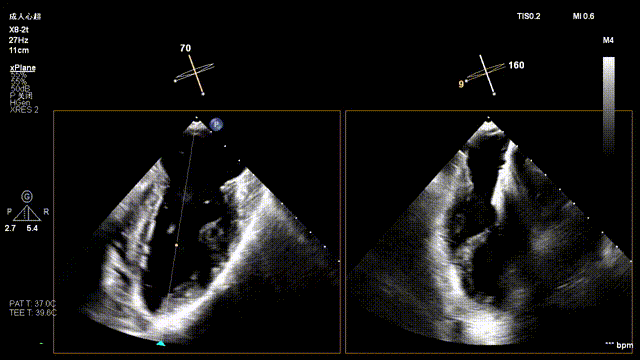

Tricuspid Valve Annuloplasty Stage:Subsequently, via the right internal jugular vein approach, the K-clip® transcatheter tricuspid valve annuloplasty system was delivered to the right atrium. With the assistance of three-dimensional ultrasound stereoscopic views, a 12T clip was successfully implanted at the posteroseptal commissural annulus of the tricuspid valve, and a 14T clip at the anteroposterior commissural annulus, achieving effective constriction of the dilated annulus. Immediate postoperative assessment demonstrated that tricuspid regurgitation was improved from severe (4+) to mild (1+) instantaneously.

1.Intraoperative baseline assessment of regurgitation severity

2.Placement of large sheath and delivery system under ultrasound guidance

3.Steer and rotate the delivery system to target the lesion, and implant the anchor screw via the 3D MPR plane

4.Land the clamping arms after orientation adjustment, and close the clamping arms slowly

5.Perform the same procedure for the second clip; the clip morphology is stable under 3D imaging

Annuloplasty Effect: The tricuspid valve annulus area was reduced from 9.96 cm² to 4.6 cm², representing a 53% decrease in annulus area.

Preoperative regurgitation (severe)

Postoperative regurgitation (trivial)

Surgical Outcome: Severe tricuspid regurgitation (4+) was reduced to mild tricuspid regurgitation (1+).